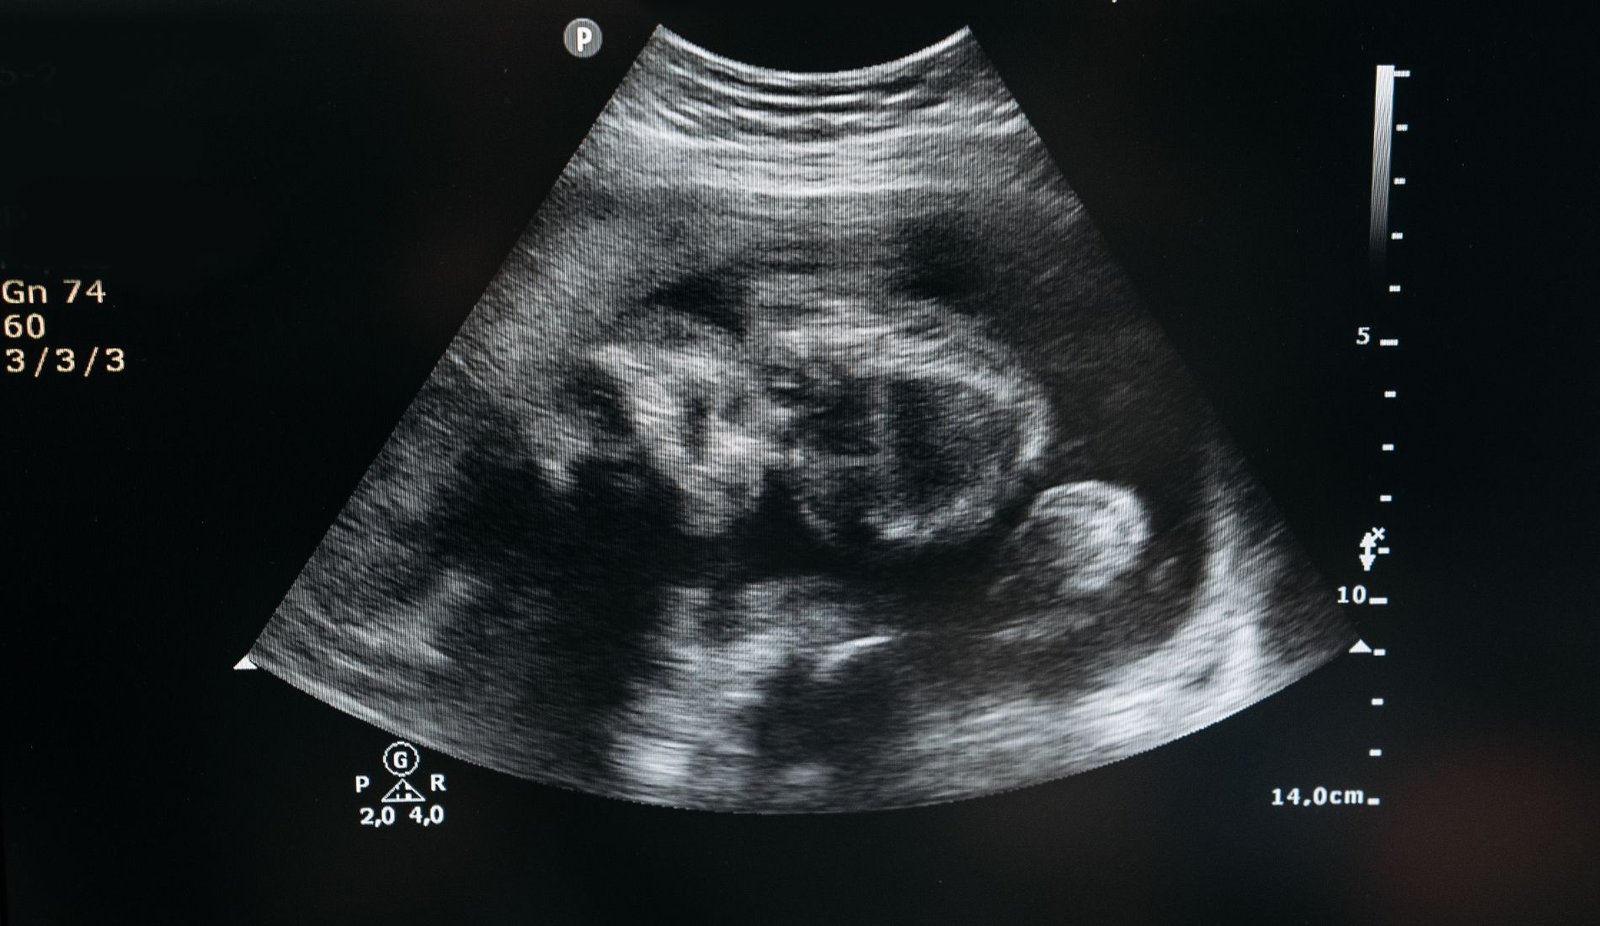

Diagnosis typically involves a combination of transvaginal ultrasound to visualize the location of the pregnancy and monitoring levels of human chorionic gonadotropin (hCG). If the gestational sac is not located within the uterus, further evaluation may be needed.